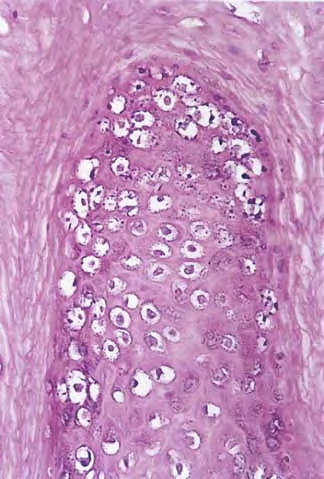

Verruca vulgaris = الثؤلول الشائع